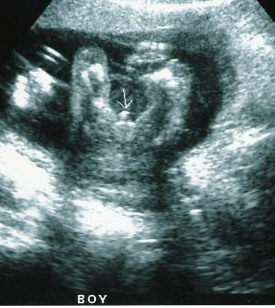

شوفي هذا عضو ولد واضح الدويره والبروز لعضوه بين رجوله

وهذا ولد بعد